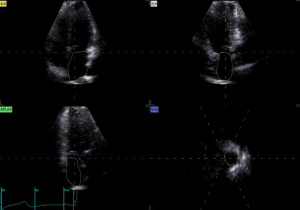

Image acquisition and data analysis of RT-3D Auto LAQ

RT-3D Auto LAQ image acquisition operation guidelines: (I) use the 4Vc matrix probe was to obtain two-dimensional images at the standard four-chamber heart section, and adjust the sector depth and gain to make the left atrium clearly visible in all the apex views; (II) Breath-hold at end-expiration; acquire 4–6 cardiac-cycle four-dimensional (4D) full-volume loops; (III) transfer to EchoPAC; select the best loop, open 4D Auto LAQ; (IV) at end-systole, place the sampling point at the mid-mitral annulus in each apical plane; align axes; (V) activate the “review” interface to check whether the LA endocardium curve automatically outlined by the system is consistent with the real endocardium. If there is any deviation, manually drag and drop the sampling line to make it coincide with the endocardium while excluding the pulmonary vein inlet and LA auricle area, then click “result” for LA volumes and strain, as shown in Figures 1-4. The LA volume parameters are divided by the body surface area (BSA) of each case to obtain the corresponding volume indices. Further calculations are performed to determine the left atrial total emptying fraction (LATEF) = (LAVmax-LAVmin)/LAVmax; left atrial passive emptying fraction (LAPEF) = (LAVmax-LAVpreA)/LAVmax; left atrial active emptying fraction (LAAEF) = (LAVpreA-LAVmin)/LAVpreA; and left atrial expansion index (LAEI) = (LAVmax-LAVmin)/LAVmin. The LA function parameters include the left atrial storage period strain (LASr), the left atrial conduit period strain (LAScd), the left atrial systolic period strain (LASct), and the corresponding left atrial storage period circumferential strain (LASr-c), left atrial ductile period circumferential strain (LAScd-c), and left atrial systolic period circumferential strain (LASct-c) (16). Among them, LAEI, LASr, and LASr-c represent the storage function of the left atrium; LAPEF, LAScd, and LAScd-c represent the function of the LA duct; and LAAEF, LASct, and LASct-c represent the active contraction pump function of the left atrium. All parameters were averaged twice.